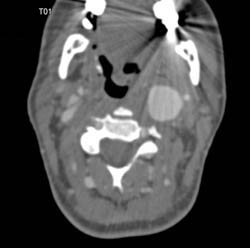

Carotid Stenosis